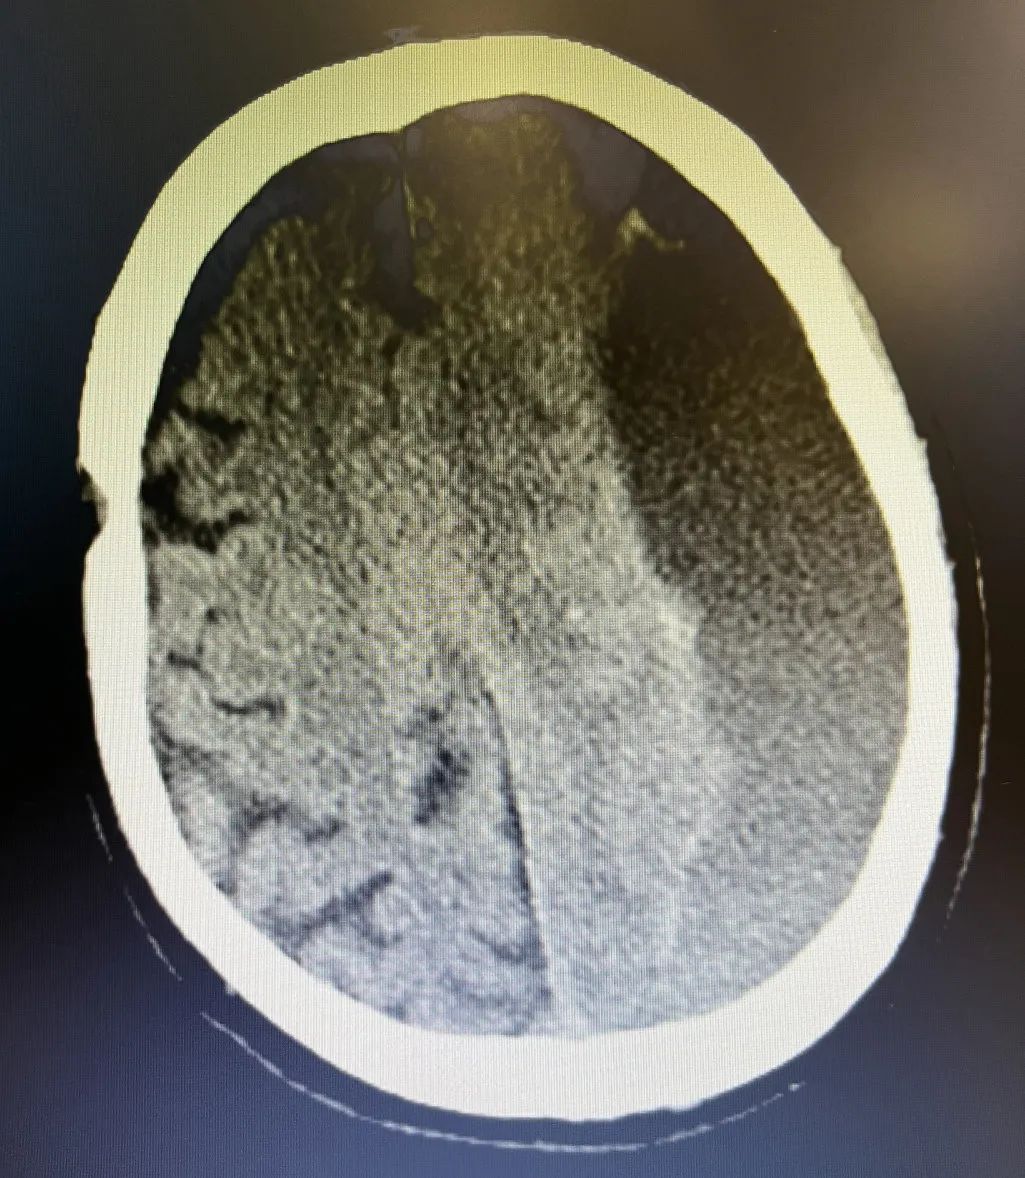

1. 左侧额顶颞枕部慢性硬膜下血肿伴大脑镰下疝形成。

2. 右侧额顶部硬膜下血肿